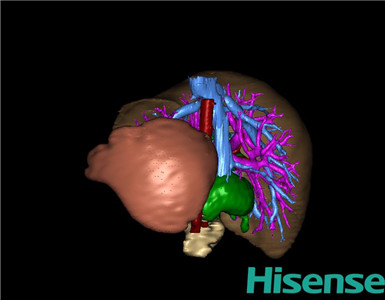

将0.625mm双源薄层CT资料的静脉期和动脉期Dicom格式文件导入海信CAS系统。

通过调节窗宽窗位调整CT序号,对肝实质,胆囊,下腔静脉,肿瘤,肝动脉、门静脉及肝静脉等进行三维重建;系统自动计算肝脏体积。

术前三维重建:

重建图片